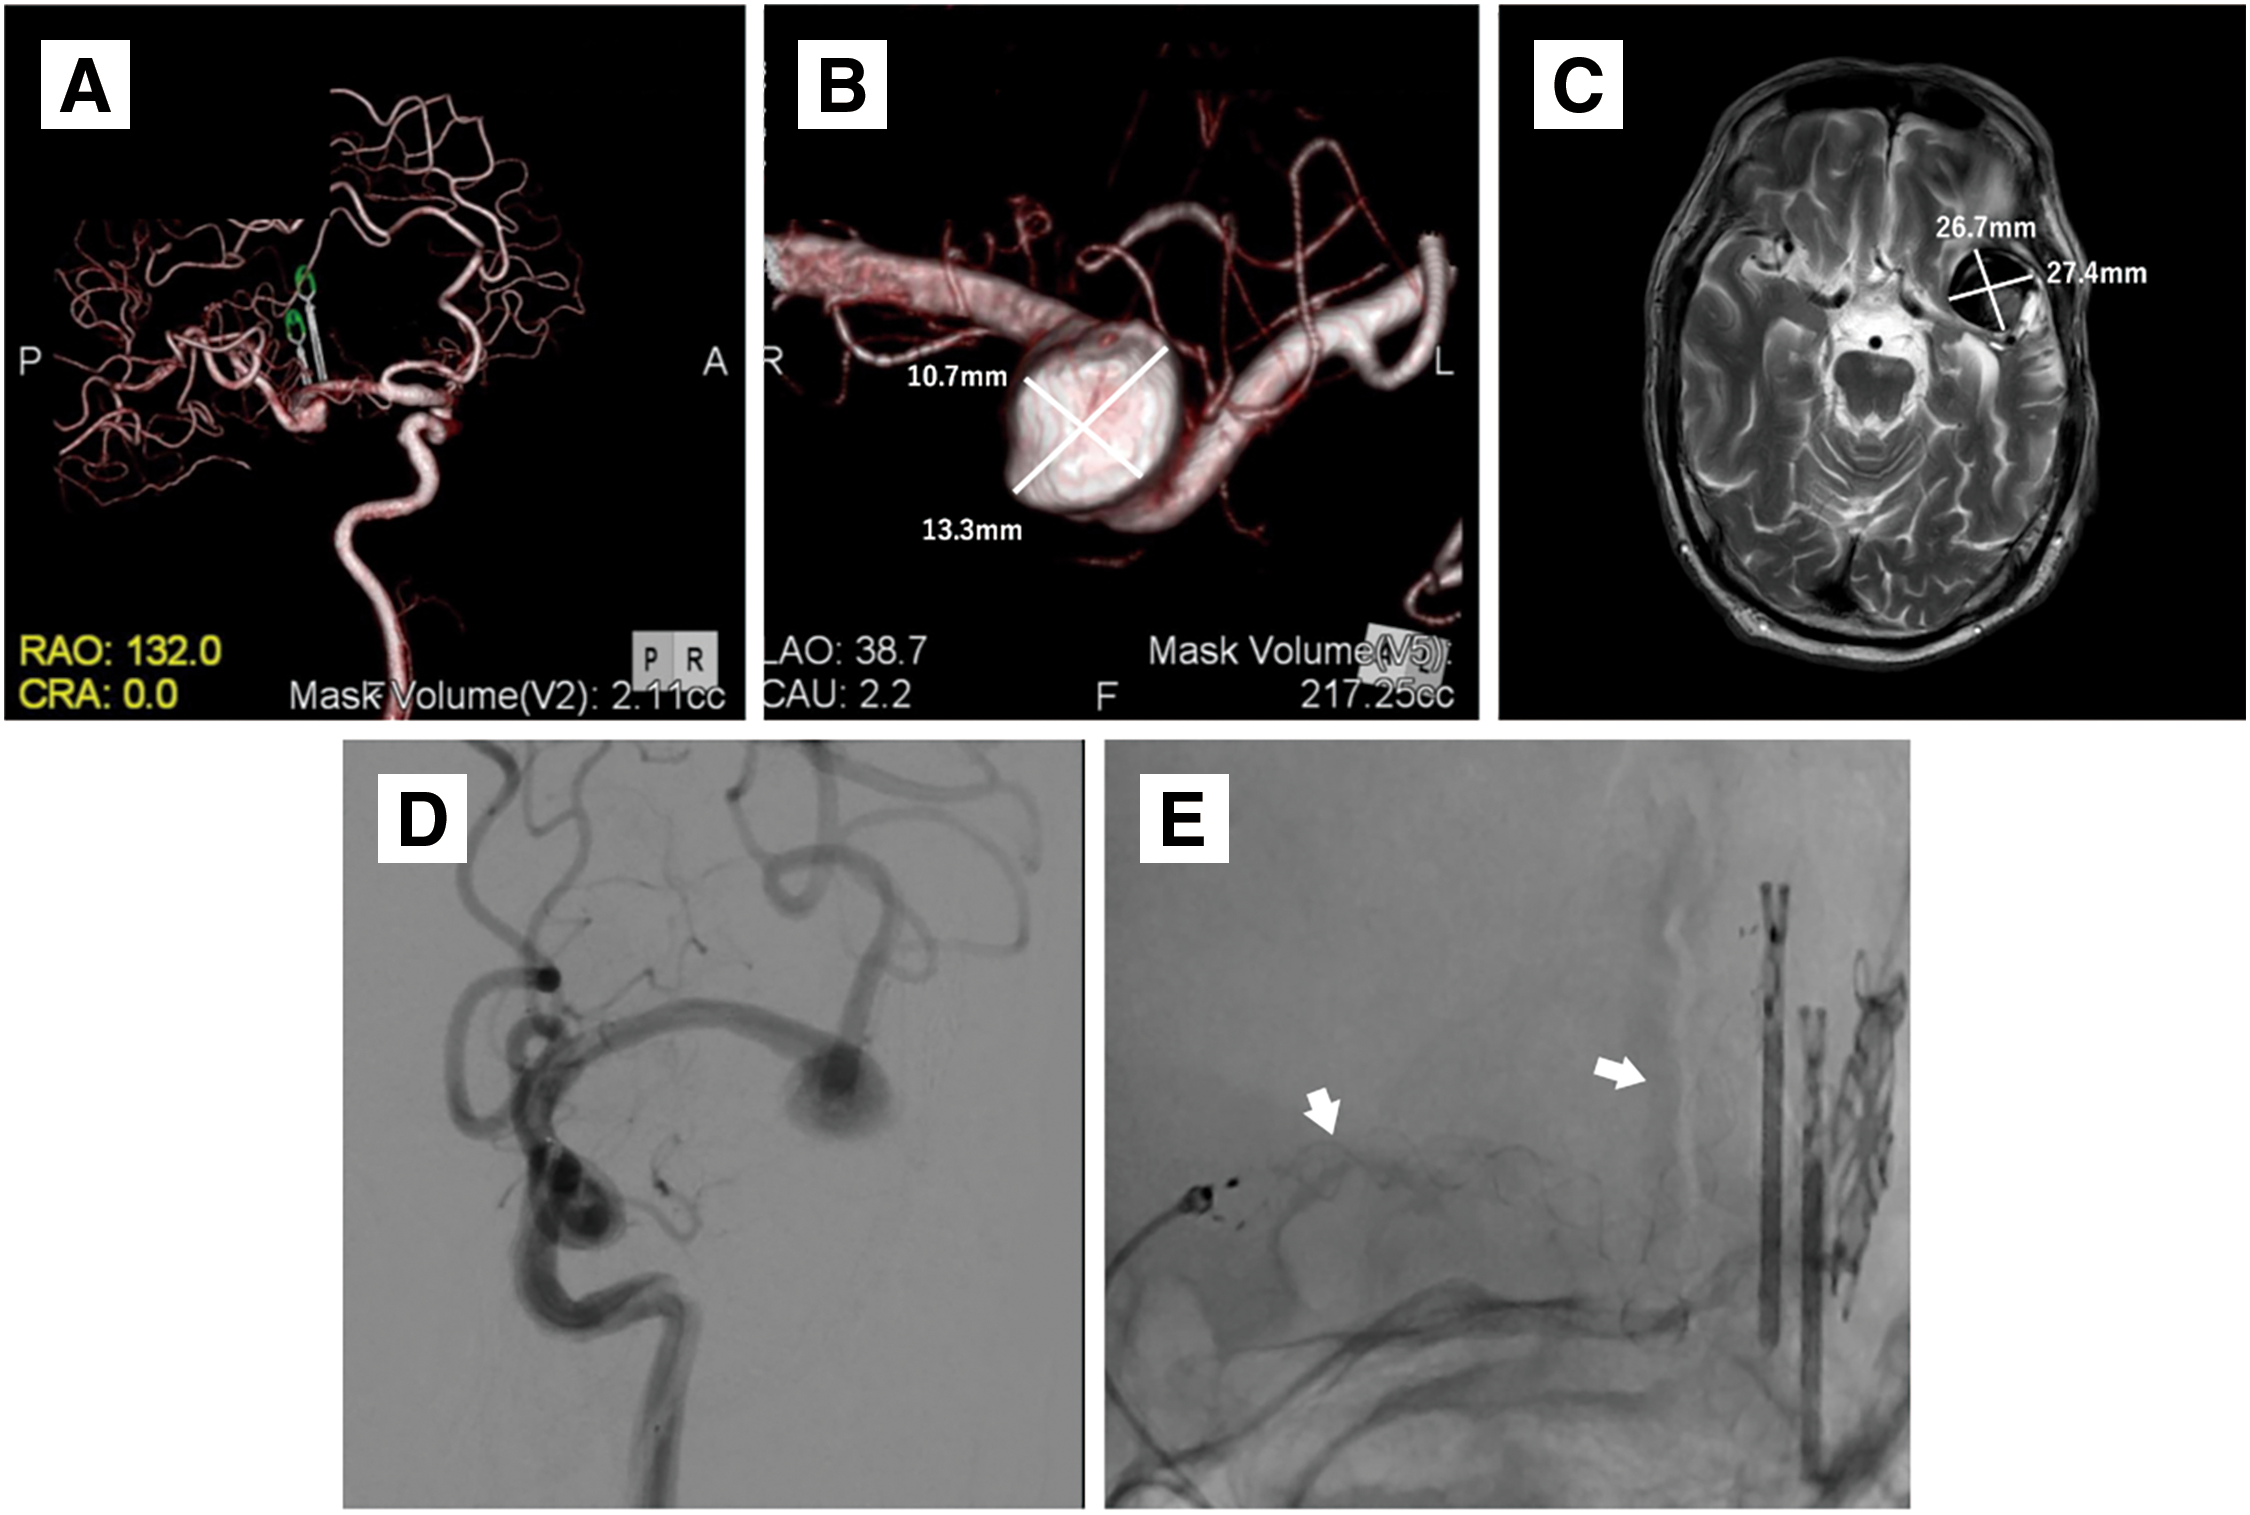

A 72-year-old man was referred to our hospital for a left MCA large aneurysm on MRI, which was associated with transient left visual field disorder. Angiography revealed a 15-mm diameter aneurysm (Fig. 1A). The MCA aneurysm was clipped partially, due to the presence of significant arteriosclerosis (Fig. 1B). The residual aneurysm gradually increased in size (Fig. 1C–1E). Two years after the clipping, he started taking 100 mg/day aspirin because of amaurosis fugax on the left side. Four years after the clipping, he developed cerebral infarction in the left MCA territory and was treated at a different hospital (Fig. 2A and 2B). A closer MRI revealed thrombosis within the aneurysm, leading to a diagnosis of cerebral embolism due to thrombus in the aneurysm. The patient was also added with clopidogrel 75 mg/day. Eight years after the clipping, another stroke occurred in the left MCA territory, resulting in dysarthria and motor aphasia (Fig. 2C and 2D). Because the aneurysm continued to gradually increase in size, the patient was referred to our hospital 8 years after the clipping. Cerebral angiography revealed the large left MCA aneurysm with a maximum dome diameter of 13 mm (Fig. 3A and 3B), and the left M2 superior trunk was occluded. The maximum dome diameter of the aneurysmal measured on MRI was 27 mm, and the majority of the aneurysm was thought to be thrombosed (Fig. 3C). Although the patient did not show symptoms related to the mass effect of the thrombosed aneurysm, repeated cerebral infarctions developed due to intra-aneurysmal thrombosis, despite dual antiplatelet therapy (DAPT), indicating the need for surgical intervention. The left M2 had only 1 inferior trunk due to occlusion and had developed into a sidewall aneurysm, which made FD placement more favorable. Therefore, FD placement was performed in the same year.

Endovascular treatment: Clopidogrel (75 mg/day) was replaced with prasugrel (3.75 mg/day) 2 weeks before endovascular treatment. Under general anesthesia, a 5 Fr guiding sheath (Fubuki; Asahi Intecc, Aichi, Japan) was introduced after puncturing the right radial artery. Intravenous heparin sodium of 4000 units was administered, and the activated clotting time was controlled to more than 200 seconds. A combination of a 5F SOFIA (Terumo, Tokyo, Japan), Headway27 (Terumo), and Synchro select soft (Stryker, Kalamazoo, MI, USA) was used to navigate from the left internal carotid artery (ICA) to the left M2. A FRED flow diverter (Terumo) 4.0–44 mm was deployed from the left M2 inferior trunk. The FRED was anchored at the M2 segment, and the system pull technique was used to obtain the shortest possible course within the mass and deployed at the proximal M1 segment to the aneurysm (Fig. 3D and 3E). After deployment of the FD, cone beam CT was performed using a 5-fold diluted contrast medium to evaluate the apposition of the FD. The endovascular procedure was terminated after confirming good FD apposition. The patient was discharged on postoperative day (POD) 4 without any complications.

Post-discharge course: MRI was performed 1 month and 1 year after discharge, but no significant change was observed, including in the size of the thrombosed aneurysm (Fig. 4A and 4B). Angiography was performed 6 months after the surgery, and complete occlusion of the aneurysm O’Kelly–Marotta grading scale (OKM) Grade D was confirmed (Fig. 4C and 4D). Comparing the vascular lumen diameter inside the FD immediately after placement and 6 months later, the lumen was reduced in diameter in the proximal, mid, and distal portions of the FD, suggesting endothelialization of the device (Fig. 5A and 5B). Thus, the antiplatelet agent was reduced to a single dose of prasugrel 3.75 mg/day alone. The patient will be followed up periodically by MRI every 3 months.